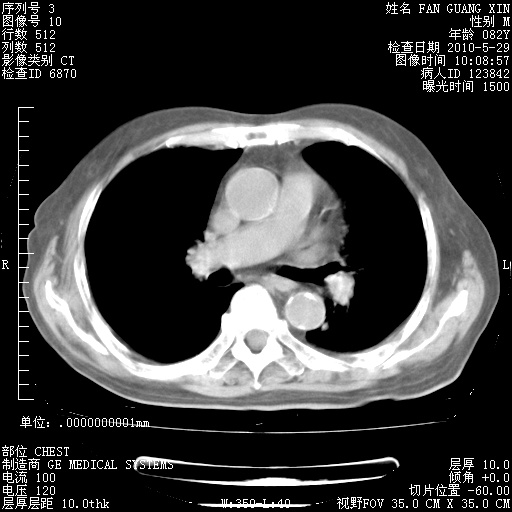

发表于 2010-5-19 19:23

还需要哪些辅助检查?我们医院排除真菌感染没有任何检验方法,胸片好像能够排除肺部真菌感染。

补充:ENA化验全部阴性。免疫五项(IgG、IgA、IgM、C3、C4)只有C4略高。

CD3+ T细胞/淋巴细胞 46% (参考值50.00~84.00%)

CD3+CD4+ T细胞/淋巴细胞 21% (参考值27.00~51.00%)

CD3+CD8+ T细胞/淋巴细胞 25% (参考值15.00~44.00%)

CD3+CD4+ T细胞/CD3+CD8+ T细胞 0.84 (参考值0.71~2.78)

T细胞亚群是治疗5天采血。